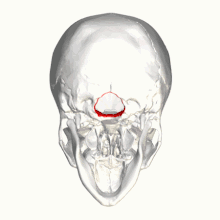

In neurology, the Chiari malformation (/kiˈɑːri/ kee-AR-ee; CM) is a structural defect in the cerebellum, characterized by a downward displacement of one or both cerebellar tonsils through the foramen magnum (the opening at the base of the skull).

By convention, the cerebellar tonsil position is measured relative to the basion-opisthion line, using sagittal T1 MRI images or sagittal CT images.[27] The selected cutoff distance for abnormal tonsil position is somewhat arbitrary, as not every person will be symptomatic at a certain amount of tonsil displacement, and the probability of symptoms and syrinx increases with greater displacement; however, greater than 5 mm is the most frequently cited cutoff number, though some consider 3–5 mm to be "borderline"; pathological signs and syrinx may occur beyond that distance.[27][28][29] One study showed little difference in cerebellar tonsil position between standard recumbent MRI and upright MRI for patients without a history of whiplash injury.[22] Neuroradiological investigation is used to first rule out any intracranial condition that could be responsible for tonsillar herniation. Neuroradiological diagnostics evaluate the severity of crowding of the neural structures within the posterior cranial fossa and their pressure against the foramen magnum. Chiari 1.5 is a term used when both brainstem and tonsillar herniation through the foramen magnum are present.[30]